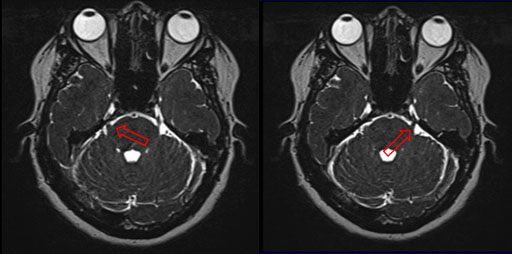

This case was evaluated by neurosurgery service with an emphasis on radiosurgery in different hospitals in the country, where in the medical board of the case, and in accordance with the analysis of the brain magnetic resonance (Figure 2) and the patient's history, it was decided to perform CyberKnife radiosurgery in mono-fraction on the left trigeminal and subsequently treat the contralateral trigeminal.

Figure 2 Bilateral trigeminal neuralgia by contrasted brain magnetic resonance. Vascular compression can be seen in both proximal branches of the trigeminal nerve (red arrow).